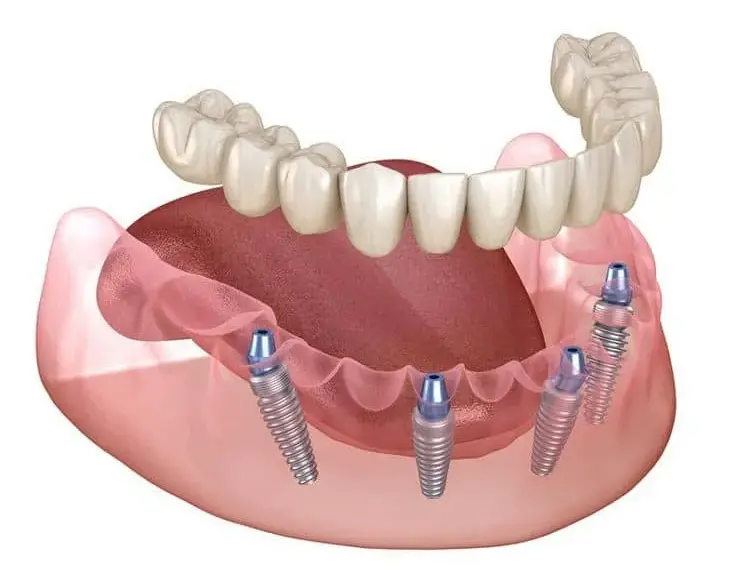

- پروتزهای متکی بر ایمپلنت

پروتز ثابت از نظر عملکرد و ظاهر، بیشترین شباهت را به دندان طبیعی دارد و به همین دلیل یکی از محبوبترین گزینهها در دندانپزشکی ترمیمی و زیبایی محسوب میشود.

- جلوگیری از تحلیل استخوان در مدلهای ایمپلنتی

مطالعات منتشرشده در American Dental Association (ADA) نشان میدهد که پروتزهای ثابت مبتنی بر ایمپلنت، بالاترین میزان رضایت بیماران را دارند.

- اوردنچرهای متحرک

در بسیاری از موارد بله، بهویژه با استفاده از ایمپلنت.